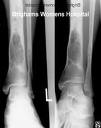

El adamantinoma aparece como una lesión lítica, excéntrica y circunscrita en radiografías simples. La corteza anterior de la tibia es el lugar más comúnmente afectado. Usualmente, la lesión tiene varios defectos líticos separados por hueso esclerótico lo cual le confiere apariencia de burbujas. Hay pérdida cortical pero poca reacción periosteal. La lesión puede llegar a atravesar la corteza y extenderse al tejido blando. Puede haber múltiples lesiones junto a tejido normal. Estudios de resonancia nuclear magnética (RNM) ayudan a determinar el grado de envolvimiento extraóseo e intraóseo. El diagnostico diferencial radiológico incluye displasia osteofibrosa, displasia fibrosa, quiste óseo aneurismático (QOA), fibroma condromixoide y condrosarcoma.